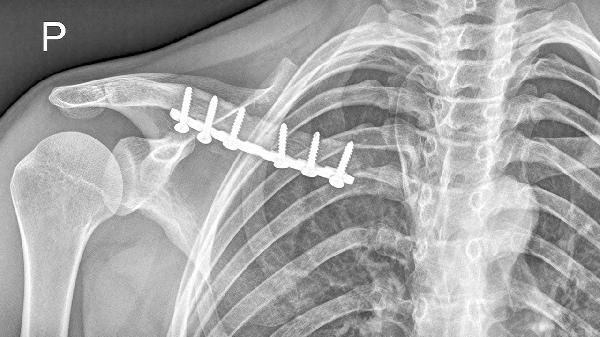

八字绷带固定者需维持肩关节制动3-4周,期间建议使用吸管或斜面餐具。手术内固定患者2周后可在支具保护下进行抓握训练,逐步过渡到持勺动作。

伤后2周开始手指屈伸及腕关节活动,3周后增加肘关节屈曲训练。上肢肌力恢复至3级以上时,可尝试用健侧手托扶患侧前臂完成送食动作。